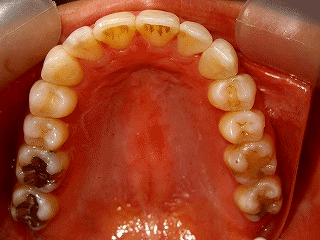

上顎前突(非抜歯)

術前